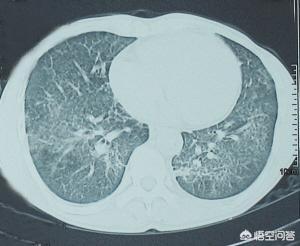

2.細菌性肺炎

異なる細菌による肺炎の臨床症状は、病原体や宿主の免疫状態(例えばグラム陰性菌)によってかなり異なる。一般的な症状としては、発熱、咳、痰、膿性または血性の痰、胸痛の有無があり、重症の場合は呼吸困難、呼吸数増加、鼻汁がみられる。

3.ニューモシスチス・カリニ肺炎

症状には、息切れ、発熱、空咳があり、このうち息切れと空咳は特異的なものである。 AIDS患者の経過は緩徐で、体格の減少、寝汗、リンパ節腫大、全身倦怠感から始まり、上記の呼吸器症状が数週間から数ヵ月続く。未治療での死亡の100%は呼吸不全によるものである。本疾患は重篤な症状を示すが、肺徴候はまれで、ほとんどの患者は肺の聴診で異常を認めない。

- カリニ肺炎

主な症状は、発熱、乾いた咳、胸のつかえ、徐々に悪化する呼吸困難である。

エイズの後期は、主に免疫機能の低下により、あらゆる種類の感染症にかかりやすくなり、普通の人には感染しない病原体も、エイズの後期には致命的な病気になります。例えば、ニューモシスチス・カリニ肺炎は、主な症状は発熱、乾いた咳で、治療しなければ、すぐに低酸素症になり、活動後に息切れしたり、あるいは完全に動けなくなり、治療が適時に行われなければ、呼吸不全で死亡します。